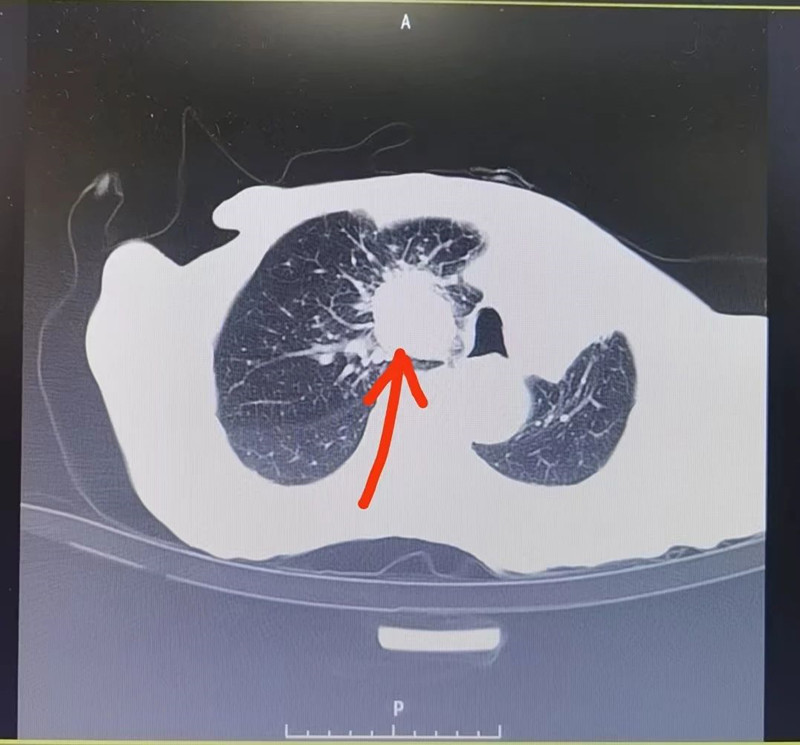

术前CT显示

肺门肿瘤染色明显(术前)